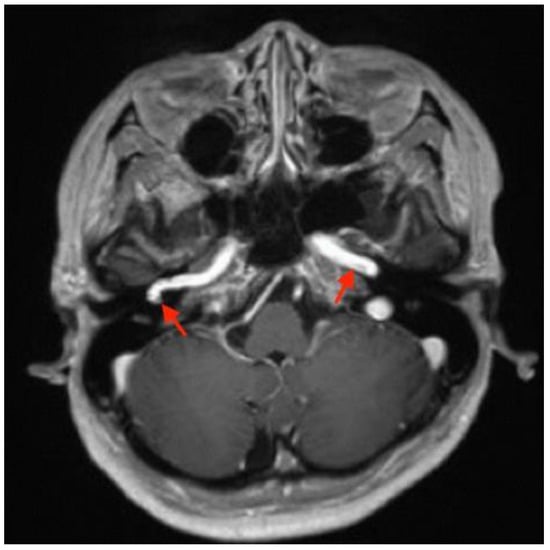

2. Case Report